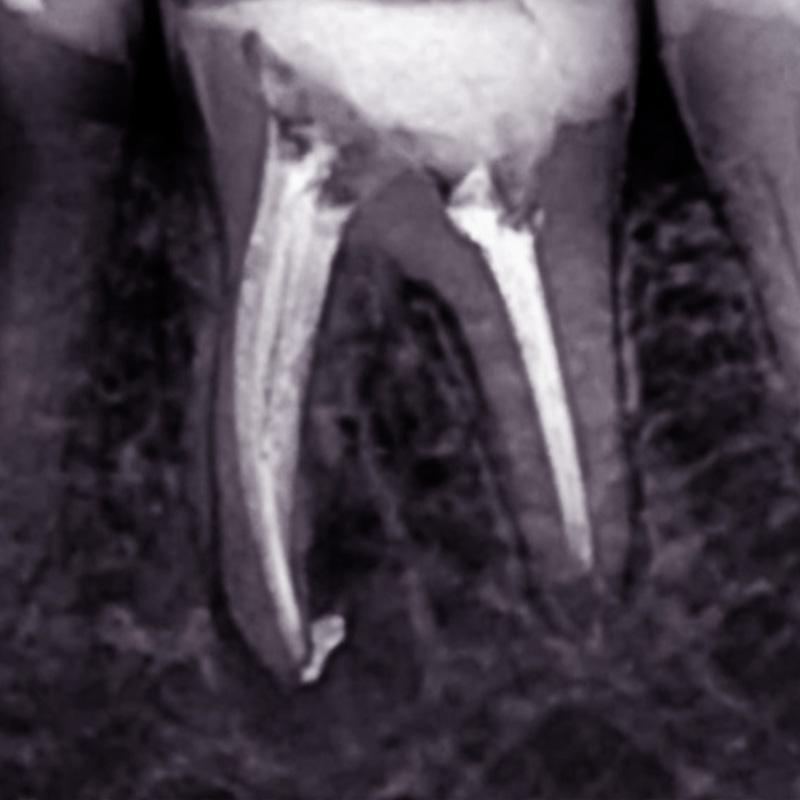

Лечение хронического фиброзного пульпита 13 зубаСмотреть работуСрок лечения:2 часа (2 посещения)Сумма лечения:15 350 руб.